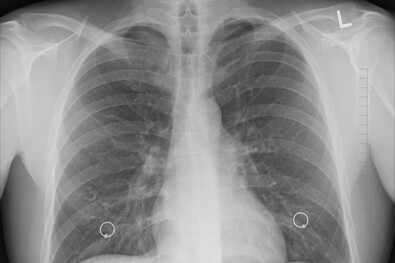

A 2000-es évek elején Romániában még több tízezerre volt tehető a tuberkulózisban szenvedők száma, és nagyon sok ember életét követelte ez a betegség – mondta el Alexandru Rafila egészségügyi miniszter a tébécé elleni küzdelem világnapján szervezett konferencián.

A miniszter emlékeztetett, hogy különböző intézkedések révén néhány év alatt sikerült megfordítani a 2003-ig tartó emelkedést, és huszonkét év alatt több mint háromszorosával csökkent a tuberkulózisos esetek száma Romániában, a 0 és 14 év közötti gyerekek esetében a csökkenés még jelentősebb.

Rafila ugyanakkor felhívta a figyelmet, hogy globális szinten a tuberkulózisos esetek száma ismét enyhe növekedésnek indult a koronavírus-járványt követően, és bizonyos térségek veszélyeztetett helyzetbe kerülnek. Hangsúlyozta, hogy nem Romániáról van szó.

Az Agerpres hírügynökség tavaly június 20-án arról számolt be, hogy tuberkulózisos betegeket azonosítottak a iaşi-i tüdőgyógyászati kórház orvosai a városhoz közeli településen egy magánóvodában. Radu Crişan Dabija kórházigazgató a sajtónak akkor azt nyilatkozta, hogy a kór terjedése Románia egyik legnagyobb egészségügyi problémája. A szakember szerint a kisgyermekeknél megfelelő védelem alakítható ki, a BCG-védőoltáson kívül a kockázat számos óvintézkedéssel csökkenthető: megfelelő szellőztetés, helyes higiénia, a száj és orr eltakarása köhögés és tüsszentés közben. Az egészségnevelés továbbra is az egyik legfontosabb eszköze a megelőzésnek – szögezte le. (i.)